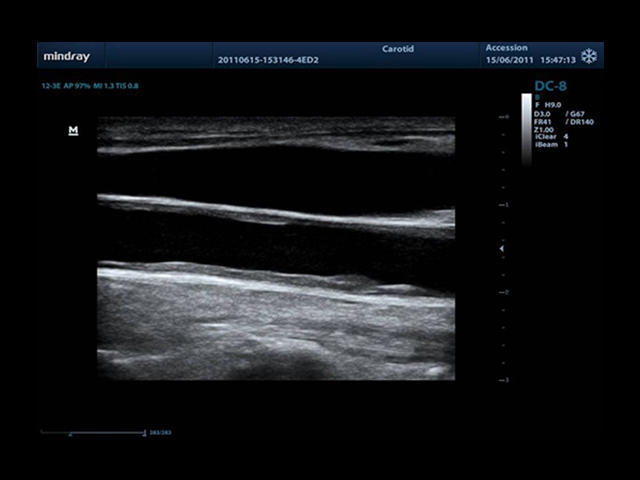

Mindray DC-8 Exp оснащен новым поколением датчиков с увеличенным количеством элементов и инновационной технологией "3T". Это позволяет достичь высокой детализации и качества изображения. Благодаря новейшей технологии iFlow, можно визуализировать даже самые мелкие сосуды и кровеносные пути.

Сверхширокополосная нелинейная обработка изображений снижает визуальные шумы на 30% по сравнению с другими системами. Технология iClear позволяет устранить зернистость изображения, а iBeam (технология пространственного компаундинга) обеспечивает высокое качество сканирования органов и тканей под различными углами.

• Auto IMT Package - измерения и анализ толщины комплекса интима-медиа (КИМ) сонной артерии.